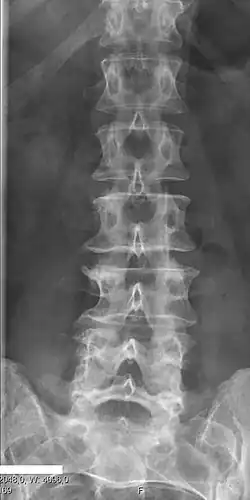

Sacralization of the fifth lumbar vertebra (or sacralization) is a congenital anomaly, in which the transverse process of the last lumbar vertebra (L5) fuses to the sacrum on one side or both, or to ilium, or both. These anomalies are observed in about 3.5 percent of people, and it is usually bilateral but can be unilateral or incomplete (ipsilateral or contralateral rudimentary facets) as well. Although sacralization may be a cause of low back pain, it is asymptomatic in many cases (especially bilateral type). Low back pain in these cases most likely occurs due to biomechanics. In sacralization, the L5-S1 intervertebral disc may be thin and narrow. This abnormality is found by X-ray.